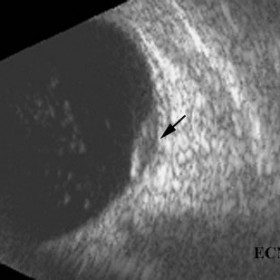

Brawny scleritis

Brawny scleritis - 10 MHz B-scan ultrasound reveals thickening of the sclera and vitreous cells (arrow).